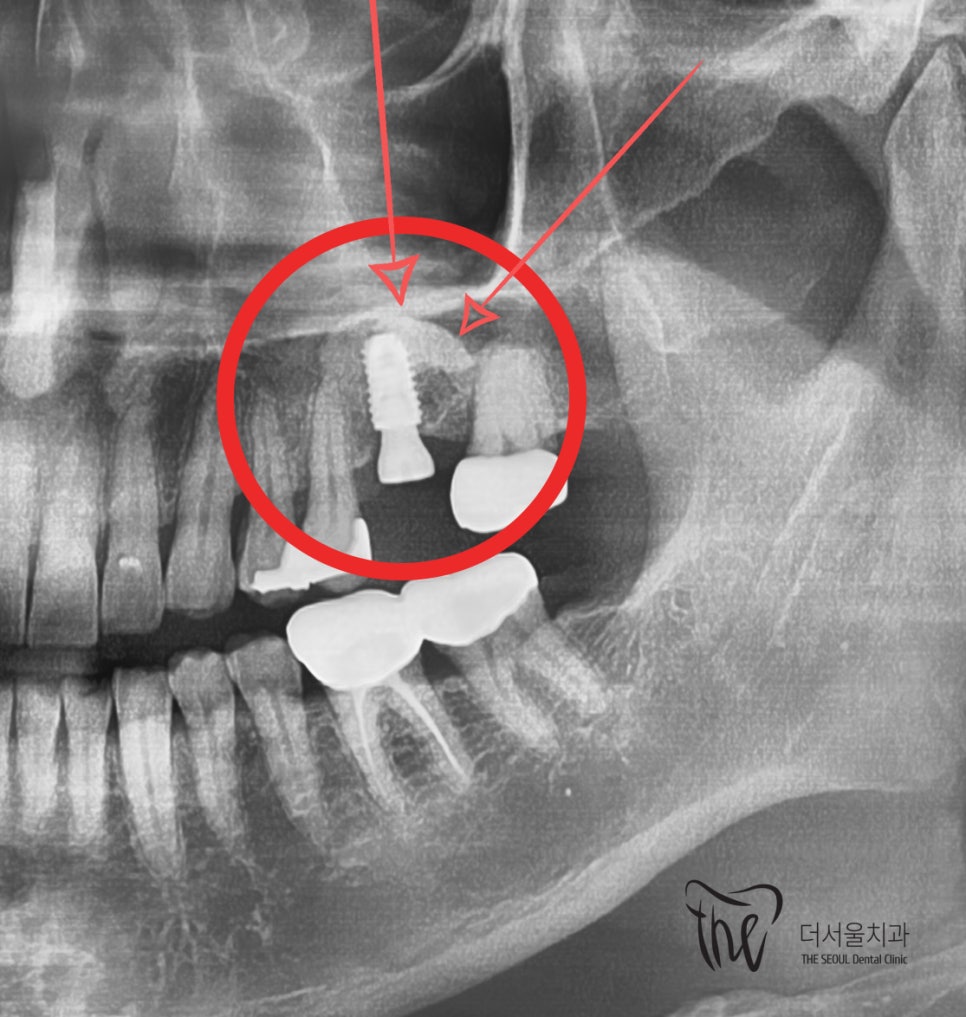

위치 및 기울기를 먼저 결정을 시켰으며

상악동과 거리가 가까운 상태였기 때문에,

- 상악동거상술(Sinus lifting)

- 골유도재생술(Guided bone regeration)

을 같이 병행하기로 진단내렸었죠.

그러면서, 기존 시술 부위는 말끔히 잘

아문것이 확인이 되었었습니다.

대략 한달 정도 걸렸던 거 같네요.

그 후, 수술 일정을 잡음에 따라서

수술을 진행했으며 앞서 설명드린 내용에 따라

상악동 거상술 및 골유도재생술을 거쳐

임플란트 흔들림 이 있었던 곳을 다시

재건시켜드렸습니다.